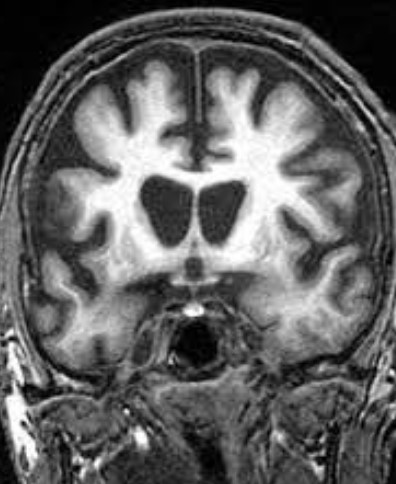

헌팅턴병

헌팅턴병은 중추신경계에 영향을 미치는 유전적 퇴행성 질환입니다. 이 병은 주로 중년기에 증상이 시작되며 신체 운동, 인지 능력, 정서에 광범위하고 심각한 영향을 미칩니다.

헌팅턴병은 HTT 유전자의 변이로 인해 발생하는데 이 유전자 변이는 염색체 4의 단완에 위치하며, 특히 CAG(시토신-아데닌-구아닌) 염기서열이 정상적인 범위를 넘어서 반복되면서 발생합니다.

정상적인 사람에서는 CAG 반복이 10-35회 사이지만, 헌팅턴병 환자에서는 36회 이상, 때로는 수백 회에 이르기도 합니다.

이러한 과도한 반복은 비정상적인 헌팅틴 단백질을 생성하며, 이 단백질은 뇌의 특정 신경세포에 손상을 입혀 점차적으로 죽음을 초래합니다.